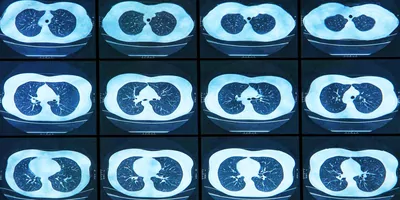

Risk factors for severe COVID-19 aren’t always straightforward. Respiratory illnesses such as asthma and chronic obstructive pulmonary disorder (COPD) are often exacerbated by viral infections, but not by COVID-19. Cystic fibrosis (CF), a condition marked by the overproduction of thick and sticky mucus in the lungs, has a more complicated relationship. While patients are at risk for serious breathing problems when exposed to influenza, they often fare better than others with respiratory syncytial virus and COVID-19 (1).

Earlier this year, Darrell Kotton and Finn Hawkins, stem cell biologists at Boston University, made airway basal stem cells, which can differentiate to become any of the cells found in the airway, from induced pluripotent stem cells (iPSCs), creating a new airway model to help understand why patients with CF aren’t more susceptible to severe COVID-19 (2).

Wang has the “perfect platform” to disentangle how COVID-19 infects the airways of CF patients. She isolates blood or skin cells from CF patient volunteers, then turns them into iPSCs. From there, she differentiates the cells into iBCs, then epithelial airway cells that contain the patients’ CF-causing mutation. As a control, she corrects the mutation in the CF patient cells before she differentiates them into airway cells.

Once Wang has these genetically matched airway cells, she grows them in an air liquid interface culture. Cells grow on the bottom of an open box-like plate in a small amount of liquid, allowing air movement across the open top.

“By developing this method, we did viral infections like what happens in the lung when the virus comes in through the air and infects the cell. The model worked really well. The cells were very infectable. We learned a lot about how a human lung cell responds when it's first infected,” said Kotton.

Now, Wang uses this culture system to look for differences in how COVID-19 enters the CF cells and if this relates to the observed decrease in patient susceptibility. Her results are currently preliminary and need to be validated in more cell lines, but she sees some evidence of differences between the CF and non-CF cells. She plans to pin down the mechanism behind those differences by performing RNA sequencing on the cells to document any differential expression for relevant genes.